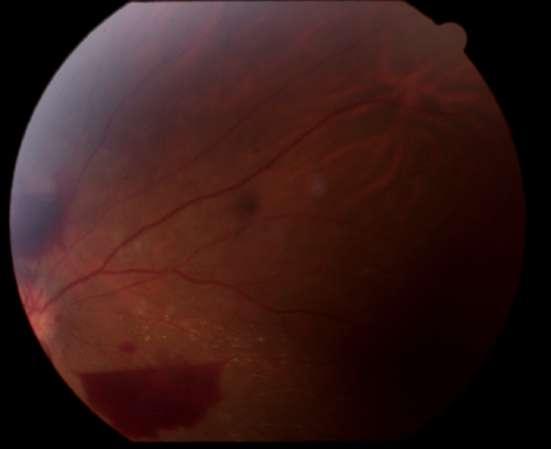

INTRAOCULAR

C D

2.E. HERIDA PENETRANTE OCULAR + CATARATA TRAUMÁTICA

Caso aportado por Dr. Matías Ramirez y Dra. María José Vergara

üPaciente 35 años le cae cuerpo extraño metálico al ojo, el cual atraviesa espesor corneal, la cápsula anterior, el cristalino, cápsula posterior

AüQuemosis conjuntival en 360º

Catarata traumática

üRuptura capsula anterior

üMasas libres

ü Herida penetrante corneal

üAumento de grosor corneal secundario a edema corneal

B

3. HERIDA PÁRPADO INFERIOR Caso aportado por Dr. Andres Torres

ü Paciente hombre se cae en el bosque enterrándose palo de madera en ojo derecho.

ü Palo de madera extraído de párpado inferior.

üQuemosis conjuntival en 360º

Palo de madera en párpado inferior

üHerida párpado inferior sin compromiso de vía lagrimal

A B C

Turn static files into dynamic content formats.

Create a flipbook

Issuu converts static files into: digital portfolios, online yearbooks, online catalogs, digital photo albums and more. Sign up and create your flipbook.